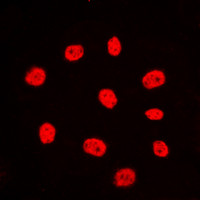

Product information "Anti-Estrogen Receptor alpha"

| Application: | WB, IHC (paraffin), ICC, IF |